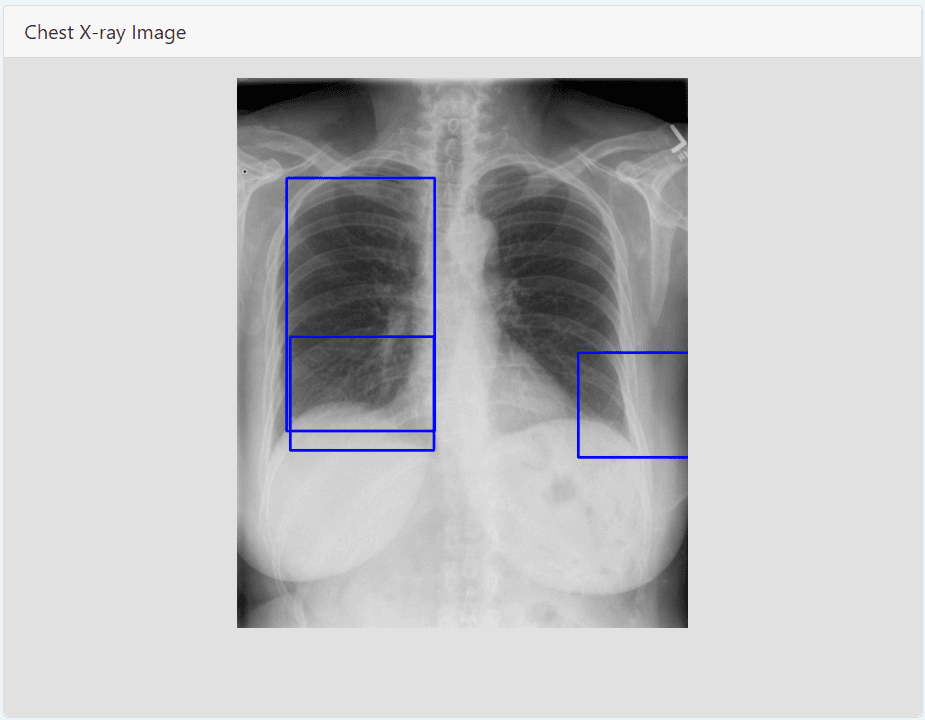

Opacification detection from Chest X-ray images and highlight areas detected on image.

Opacity localization from lungs X-Ray images and mark on images